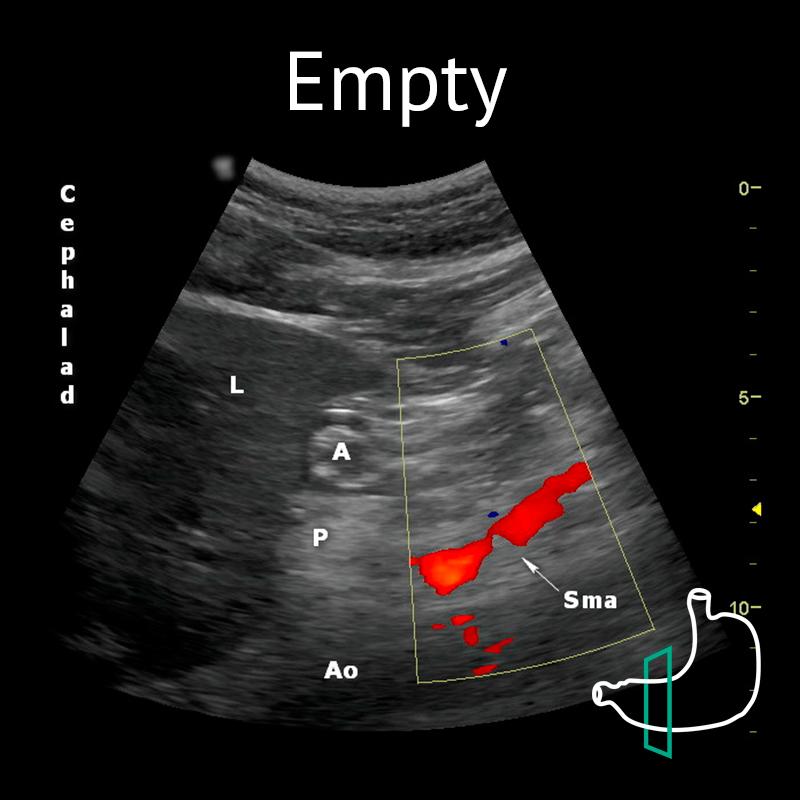

A: antrum; Ao: aorta; L: liver; P: pancreas; Sma: superior mesenteric artery